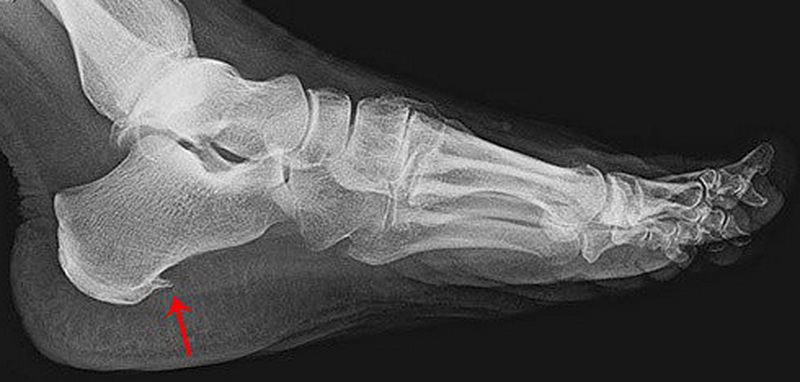

І тут криється головна іронія. При шпорі справді формується кістковий наріст — шип, який гарно видно на рентгені і який власне виглядає як шпора. Та правда в тому, що цей наріст сам по собі не болить. А точніше, болить не він. Болять дірки, які організм намагається залатати.

Але людське тіло — геніальний архітектор. Воно намагається відновитись. Формує мікрорубці, як мозолі на руках від фізичної роботи. На цих рубцях відкладається кальцій щоб зміцнити сухожилок. І саме це формує той характерний вигляд на рентгені — шпору.